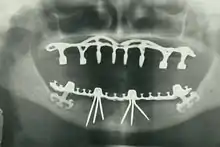

By nature of their general training, dentists, without specialization can carry out the majority of dental treatments such as restorative (fillings, crowns, bridges), prosthetic (dentures), endodontic (root canal) therapy, periodontal (gum) therapy, and extraction of teeth, as well as performing examinations, radiographs (x-rays), and diagnosis. Dentists can also prescribe medications such as antibiotics, sedatives, and any other drugs used in patient management. Depending on their licensing boards, general dentists may be required to complete additional training to perform sedation, dental implants, etc.

- Oral and maxillofacial radiology – The study and radiologic interpretation of oral and maxillofacial diseases.